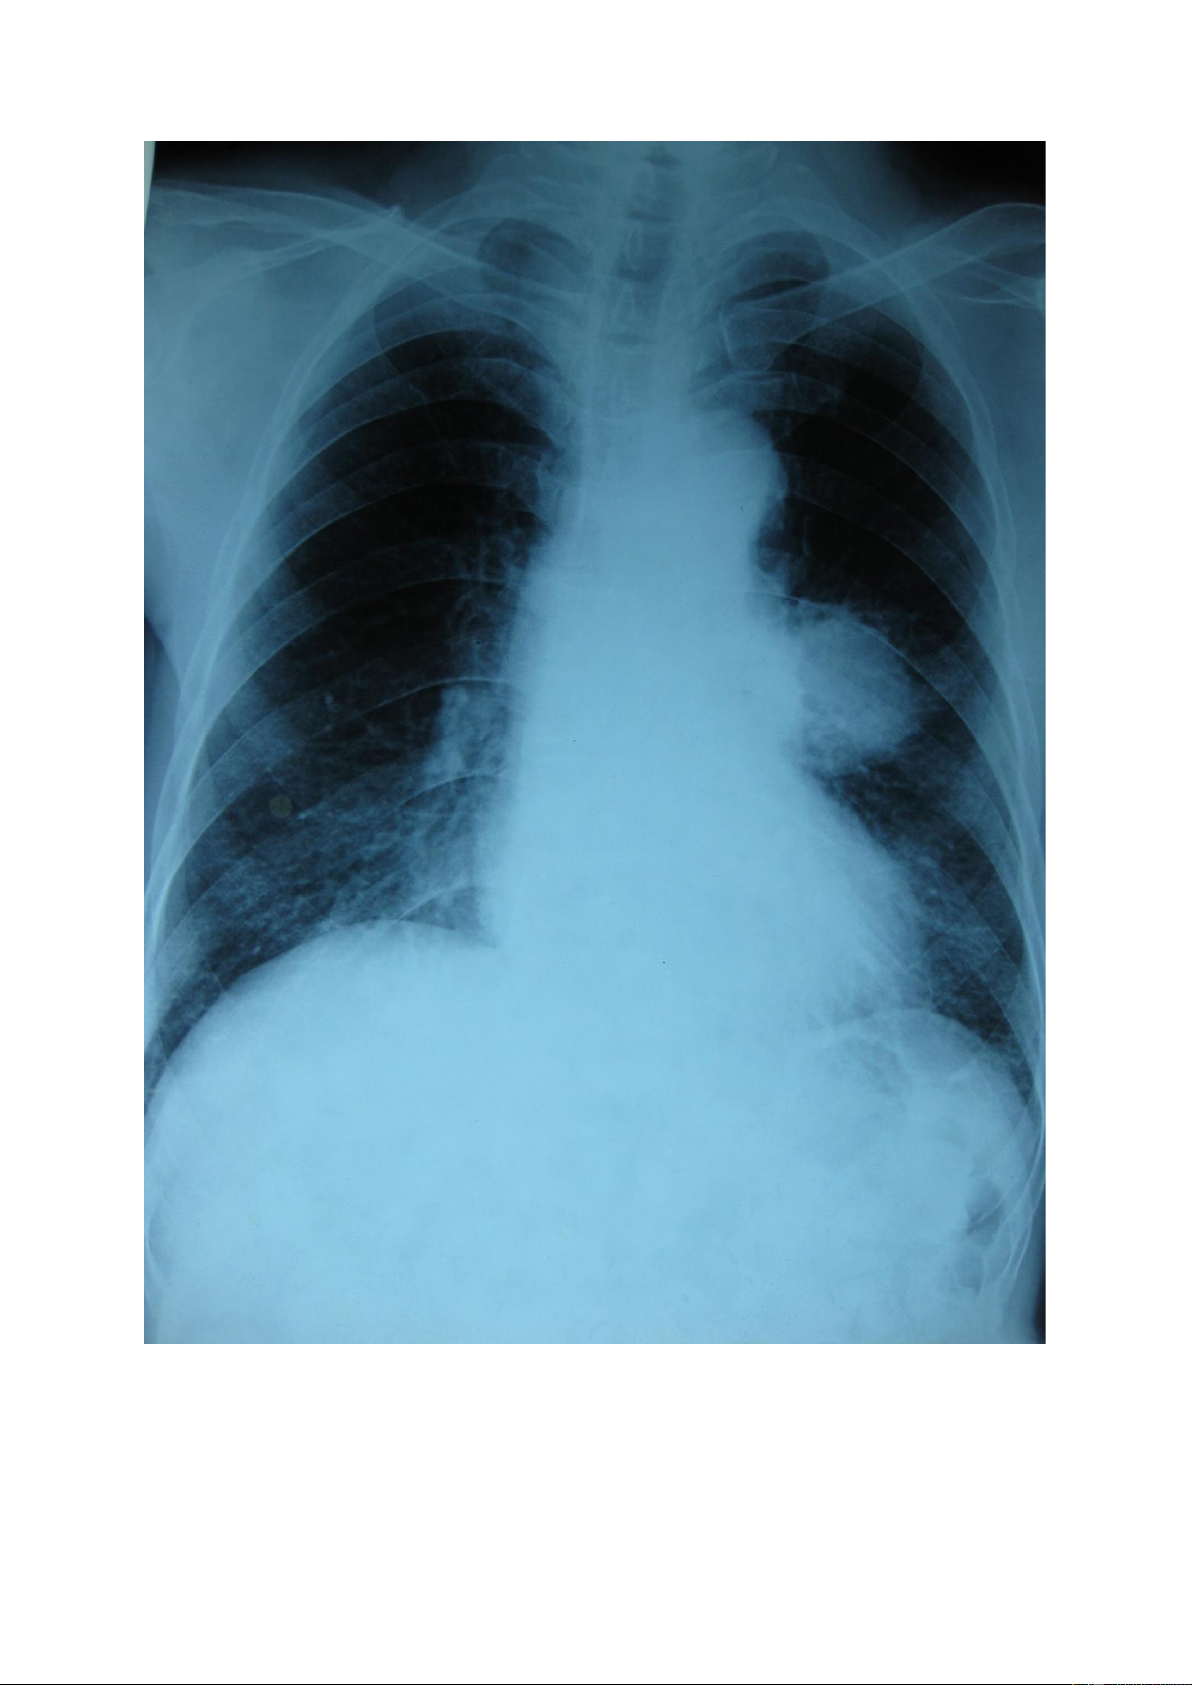

Đám mờ: là tổn thương có sự tập trung của các nốt mờ theo vùng tạo thành

hình ảnh vùng mờ không đồng đều, không rõ bờ của vùng tổn thương đó. lOMoAR cPSD| 22014077 1.5.